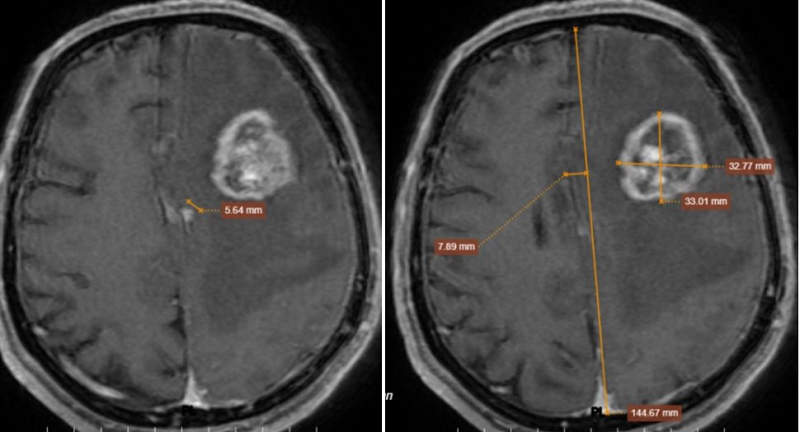

Hình ảnh MRI sọ não phát hiện một khối choán chỗ tại vùng thái dương - đỉnh trái với kích thước khoảng 32mm. Không chỉ có một khối u đơn độc, não còn xuất hiện nhiều tổn thương rải rác ở cả hai bán cầu và màng não. Tình trạng phù não lan rộng, gây chèn ép và đẩy lệch đường giữa gần 8 mm - đây là dấu hiệu nguy hiểm, có thể ảnh hưởng trực tiếp đến tính mạng.

Chụp MRI sọ não có khối choán chỗ vùng thái dương - đỉnh trái, kích thước 32x33x32mm

Trong ca bệnh này, các tổn thương não có số lượng nhiều (4-5 ổ), phân bố ở vùng vỏ và dưới vỏ não, phù não lan rộng và hình ảnh ngấm thuốc dạng viền rõ. Những đặc điểm này phù hợp với u não thứ phát, tức là u di căn từ cơ quan khác, thay vì u não nguyên phát.